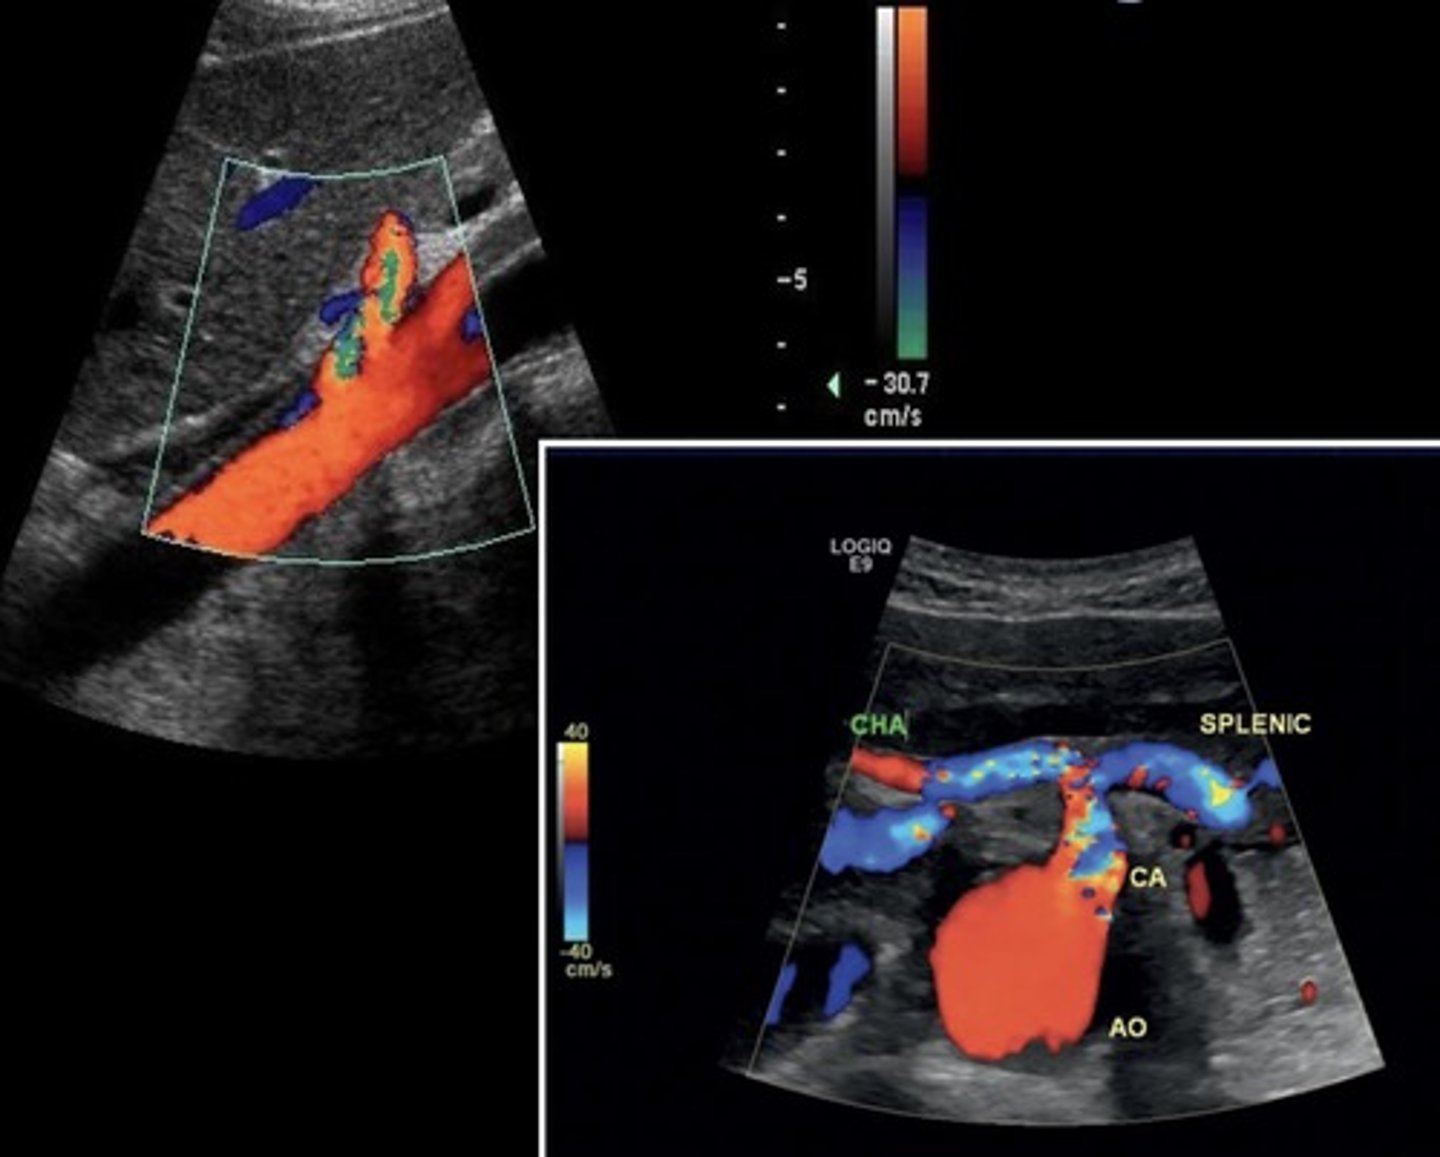

Hepatic Artery Retrograde Flow

Due to celiac artery occlusion

Blood flows towards splenic artery - RABT color pattern